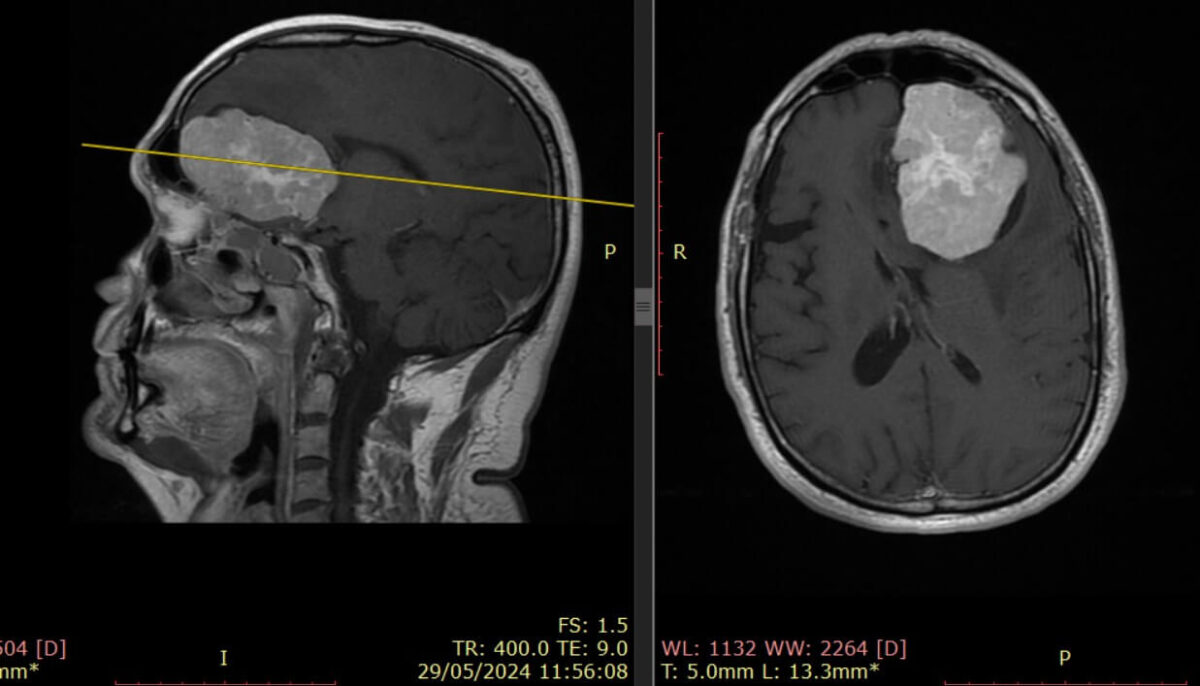

El avance en la detección del glioblastoma está dando un giro relevante gracias a una investigación que plantea una alternativa menos invasiva para pacientes y médicos. Este tipo de tumor cerebral, considerado el más agresivo en adultos, ha sido históricamente difícil de diagnosticar y seguir debido a su rápida evolución y complejidad biológica.

Actualmente, el seguimiento del glioblastoma depende principalmente de imágenes cerebrales y muestras de tejido tumoral. Sin embargo, estos métodos no siempre reflejan con precisión cómo evoluciona la enfermedad en tiempo real.